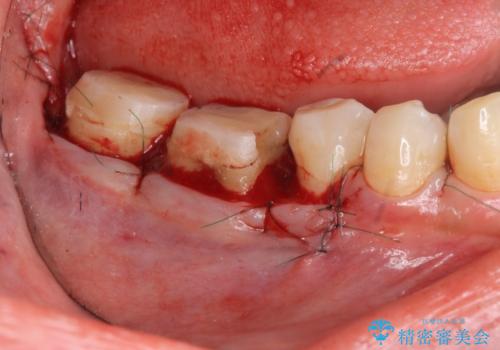

歯周外科を行うことで、歯ぐきの位置を下げ歯の高さを作り出し安定したクラウンの装着が可能となります。また同時に舌の邪魔となっていた骨隆起の除去を行うこととしました。

歯周外科に際しては、静脈内麻酔を行うことでほとんど記憶のないうちにリラックスした状態で受けていただくことができました。